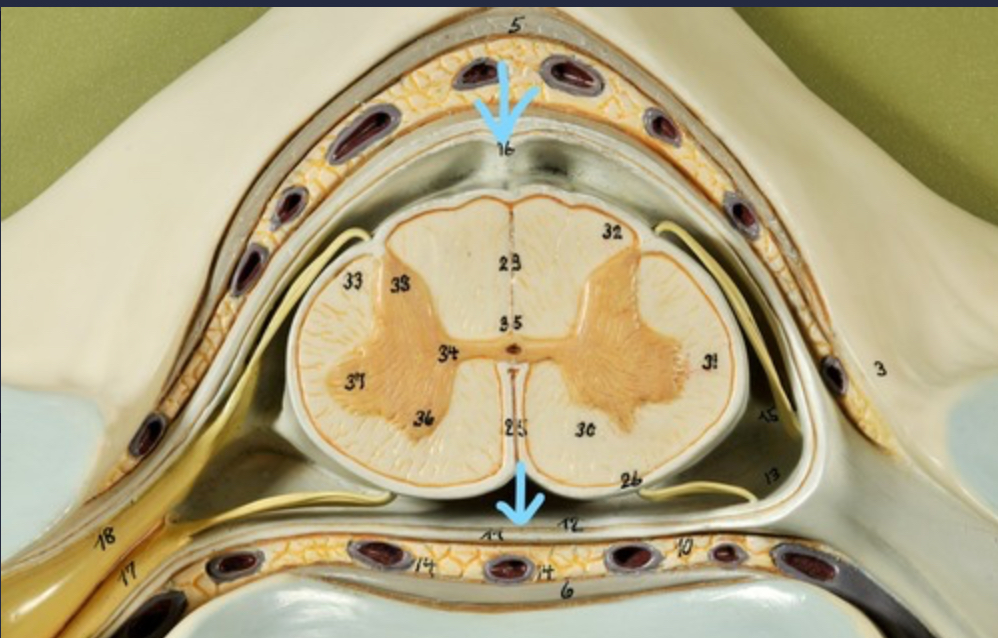

Dura mater (outermost layer)

White matter of spinal cord

Gray matter of spinal cord

Ventral horns (of gray matter)

Lateral horns

Dorsal horns

Anterior columns of white matter

Lateral columns of white matter

Posterior columns of white matter

central canal of spinal cord

Pia matter

Subarachnoid space

Arachnoid matter

Subdural space (brown line)

Dura matter

Epidural space